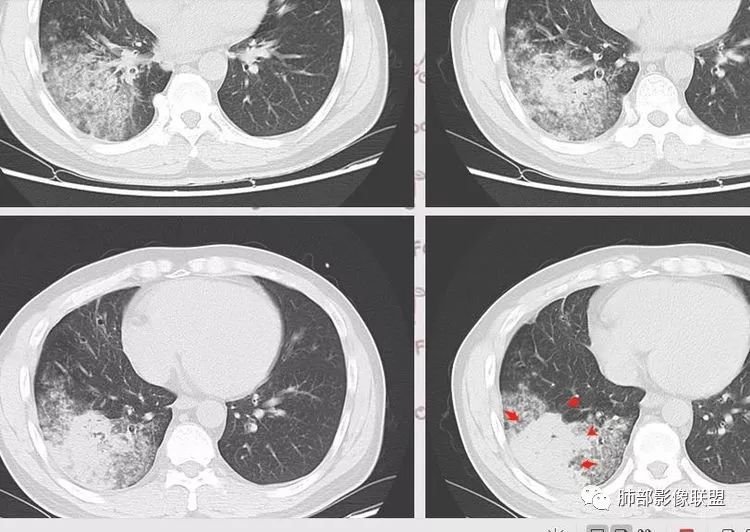

肺炭疽CT

与图5为同一病人,ct示两肺弥漫性ggo.(miyokawa r, et al.